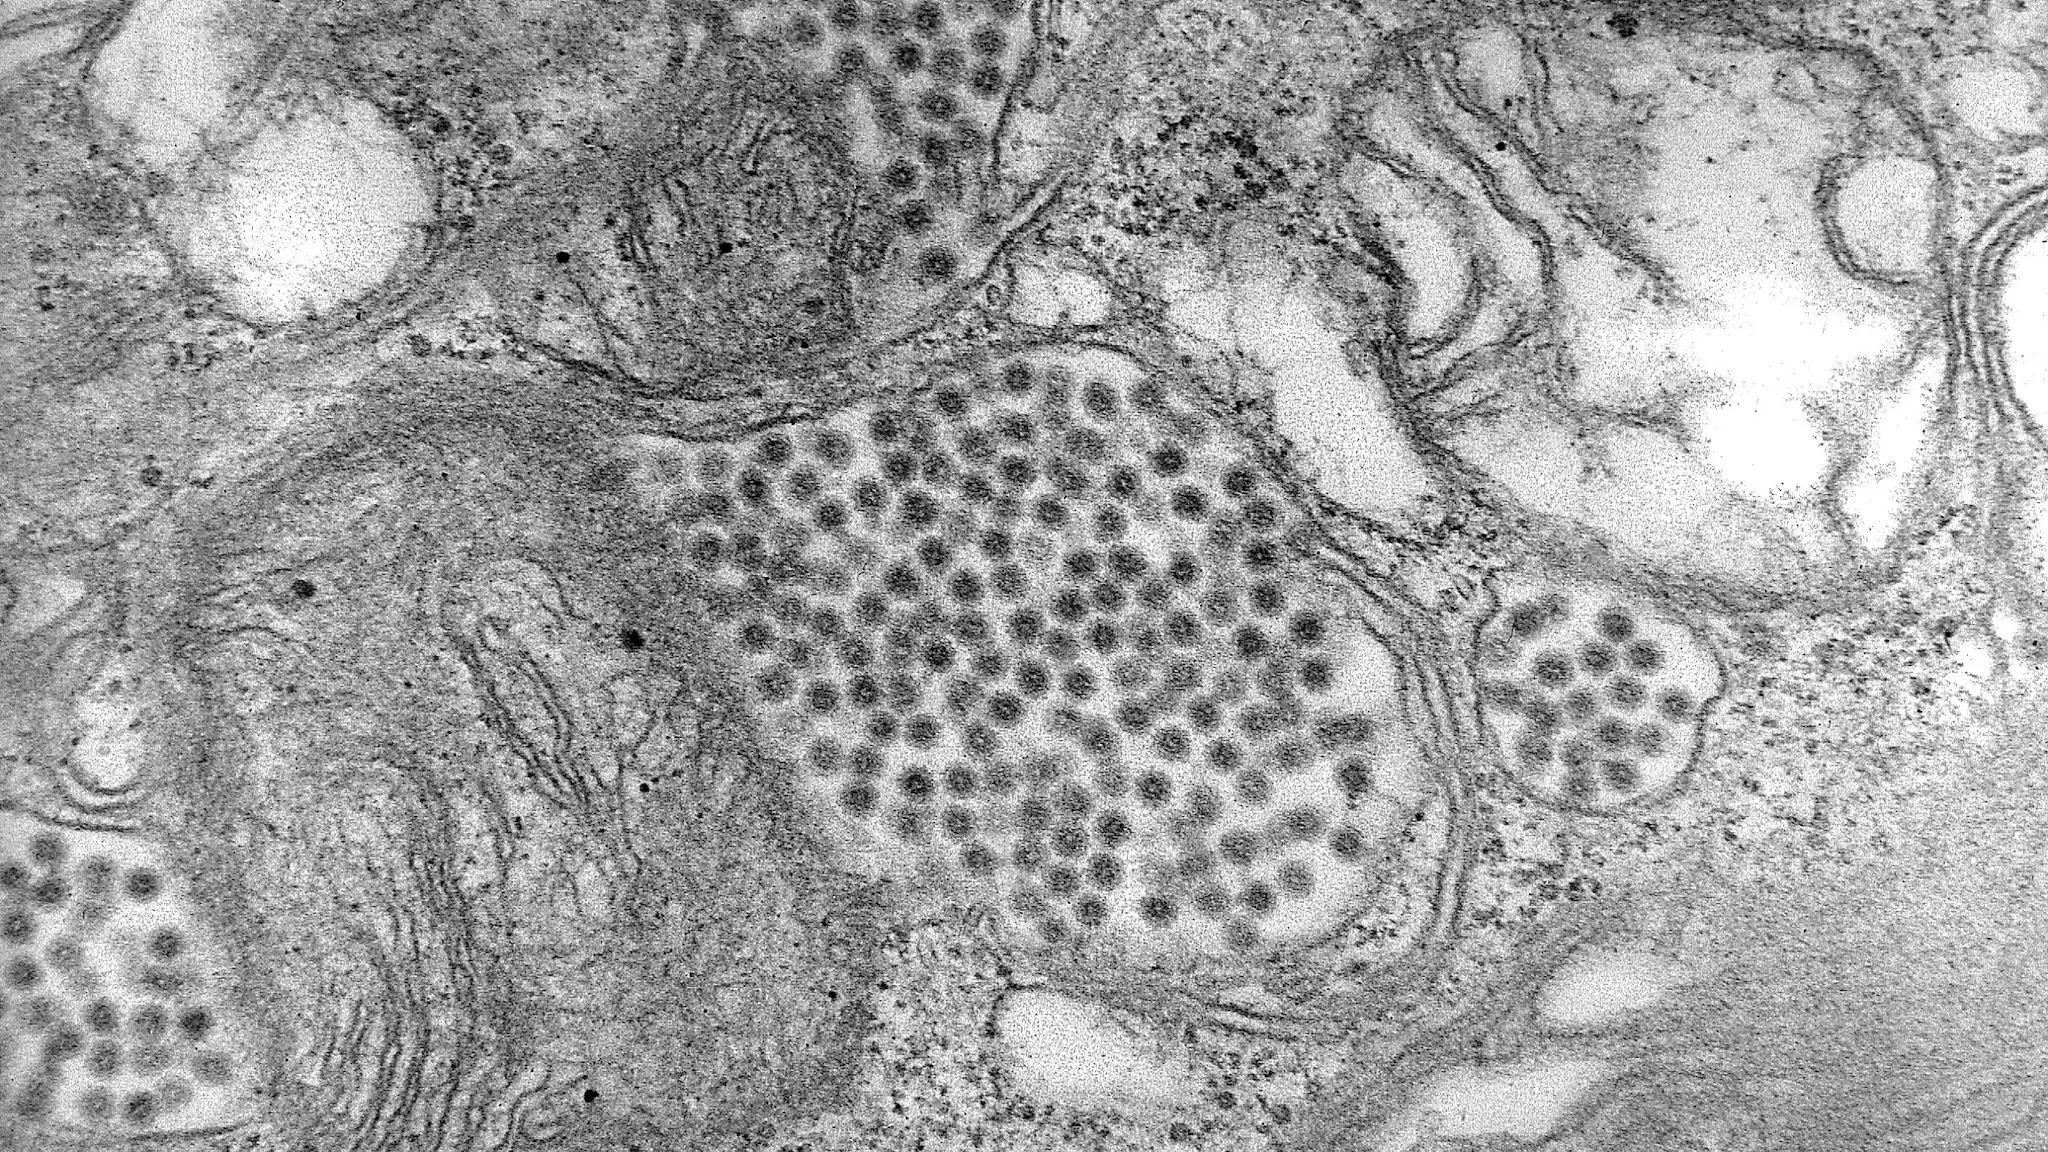

Eastern equine encephalitis virus is a member of the genus Alphavirus, family Togaviridae.

Eastern equine encephalitis virus has a single-stranded, positive-sense RNA genome. The virus particles are spherical and have a diameter of 60–65 nm.